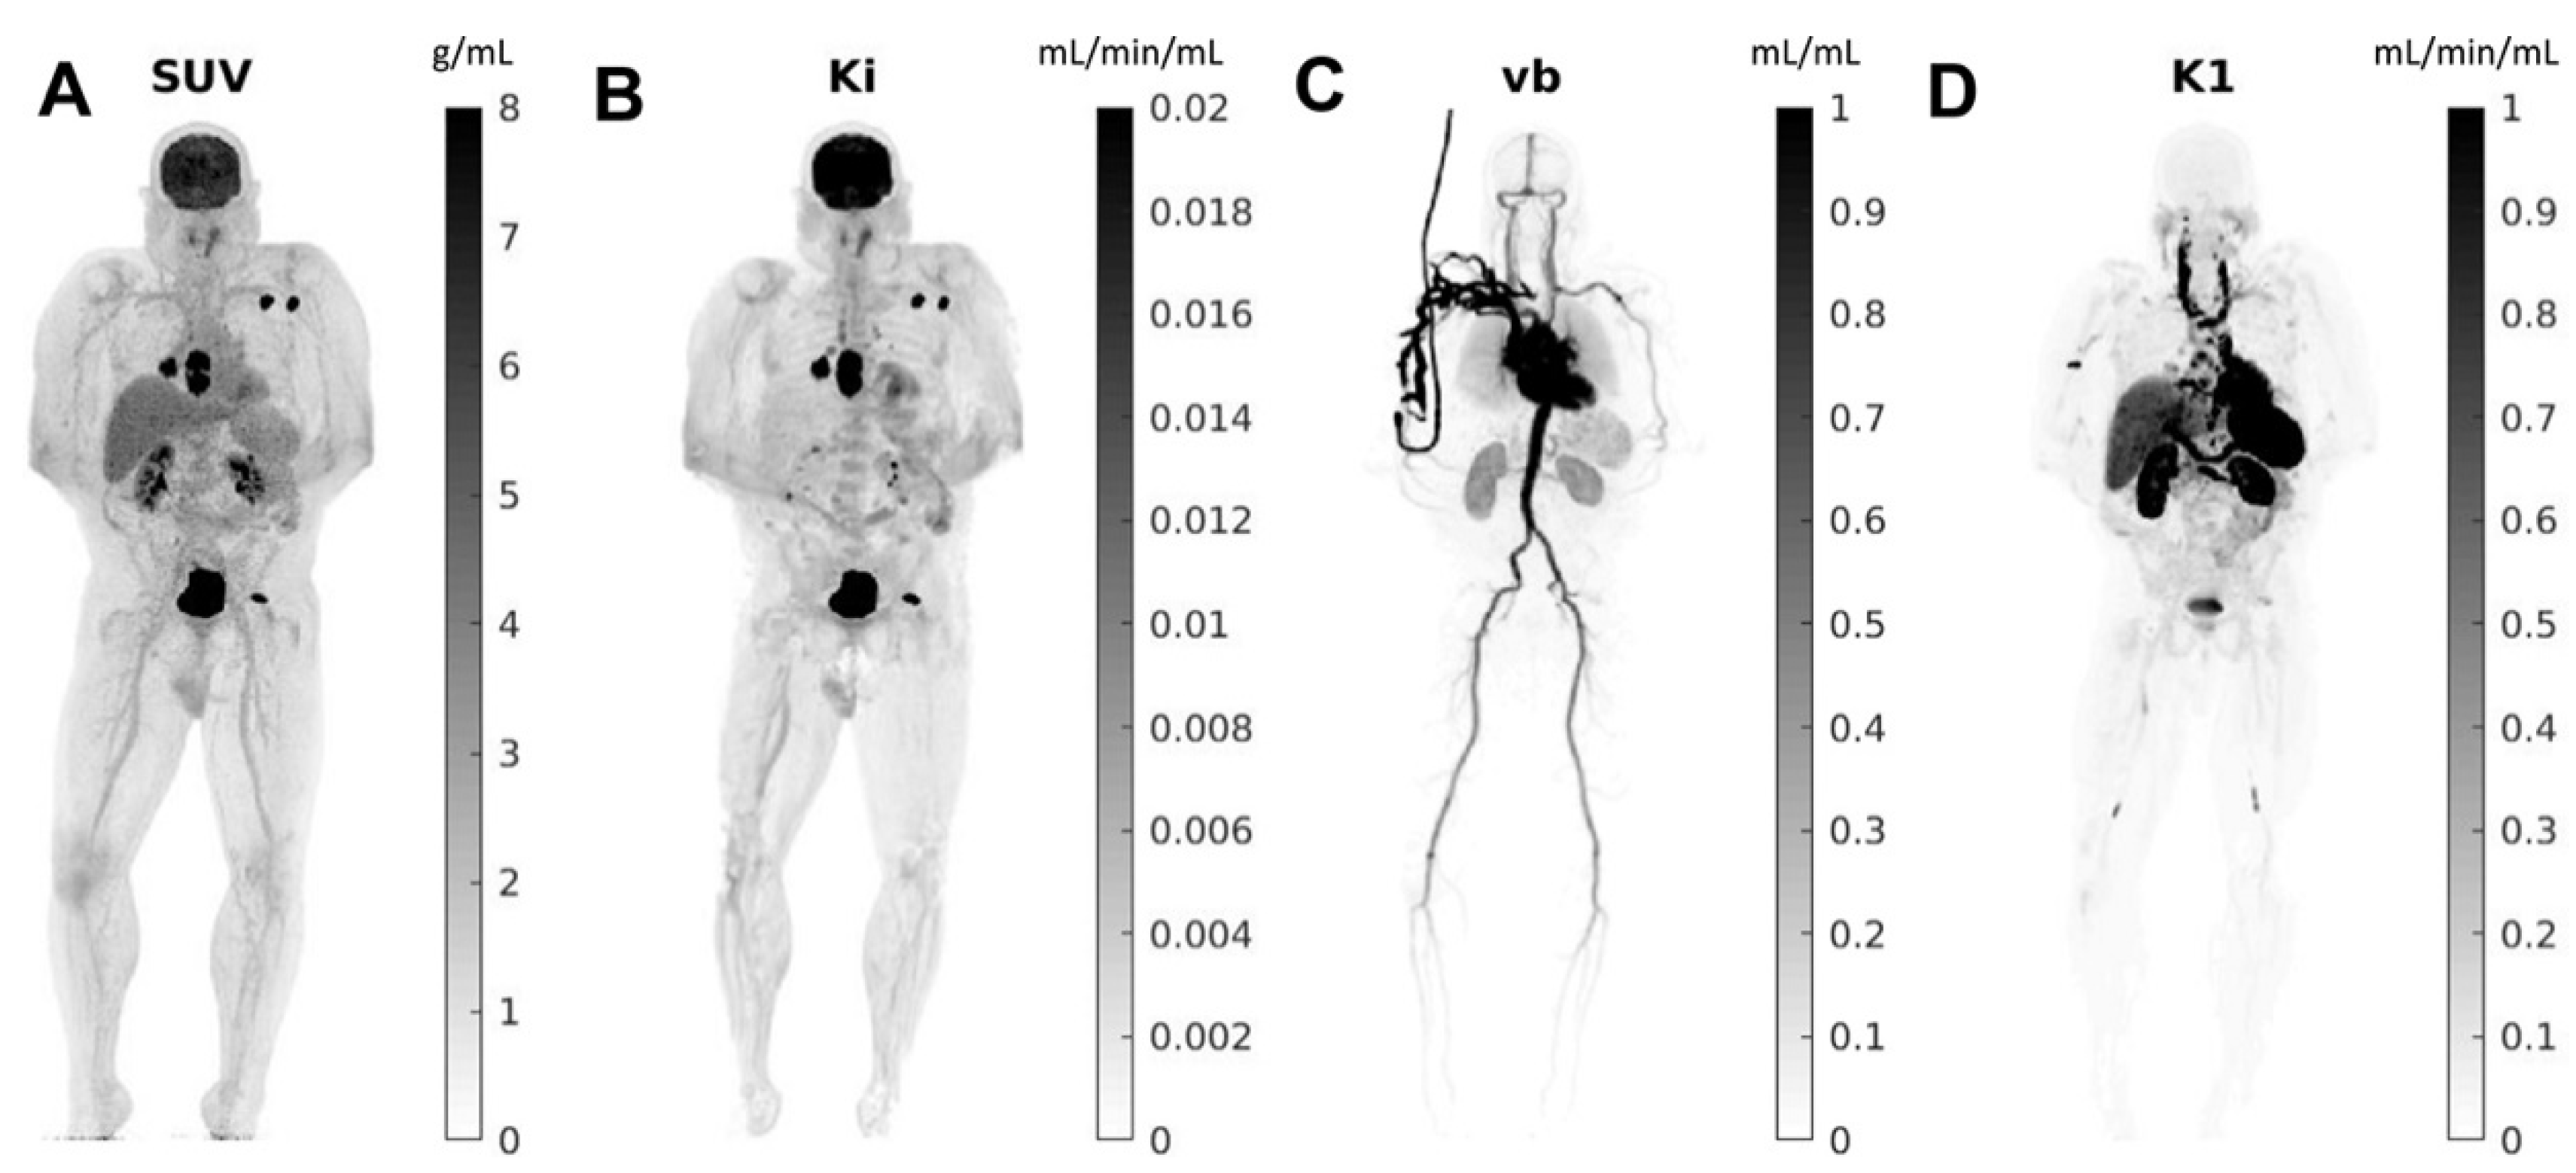

In order to extract quantitative parameters from the temporal analysis of the radiotracer distribution in voxels, novel four-dimensional (4D) dynamic whole-body PET acquisition methods have been suggested [6,7] (Figure 1). After extracting the plasma input function from the acquired images, this method utilizes a Patlak-based modeling approach to provide an estimation of kinetic parameters such as the tracer uptake rate Ki (slope) [8]. Certain authors have recognized the superiority of this 4D dynamic over the traditional three-dimensional (3D) approach in tumor characterization and distinguishing inflammation versus malignancy [9]. However, the early studies evaluated this dynamic PET methodology using a one-step conventional system (15–20 cm), which limited its ability to assess multiorgan diseases (cancer and beyond). Thus, multistep dynamic PET acquisition protocols have been tested and note various strengths and limitations. For instance, this technique allows for whole-body Ki-based analysis over a short time frame (whole-body (WB) imaging in 5–10 min). Ultimately, novel total-body PET prototypes have been successfully developed, with increased quality of 4D quantification and excellent temporal sampling (WB in 10–20 s), supporting its use in various clinical conditions.

Figure 2.

Total-body parametric images estimated from a 60-min dynamic 18F-FDG scan of a patient with metastatic cancer on the uEXPLORER: (A) SUV; (B) FDG net influx rate (Ki); (C) fractional blood volume (vb); and (D) FDG delivery rate (K1). Reprinted with permission from Ref. [19]. Copyright 2021 Elsevier.